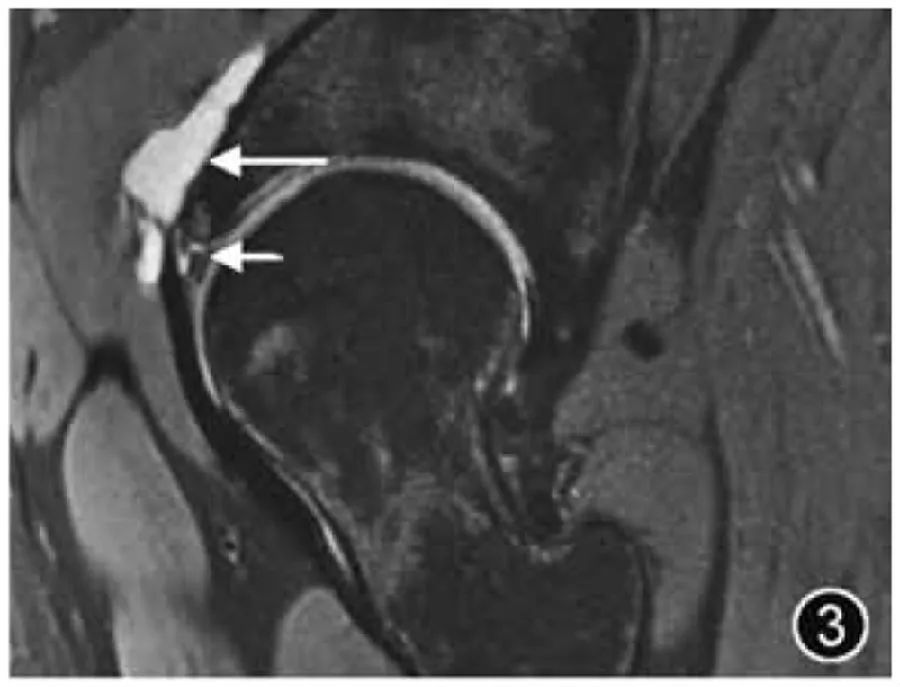

Травма вертлужной губы. Травма вертлужной губы может быть вызвана травмой или может вызвать дегенерацию, износ из-за активности суставов и чрезмерных движений, DDH, FAI и другие морфологические аномалии тазобедренного сустава могут легко привести к травме губы. Чаще всего разрывы вертлужной губы возникают в передней или передне-верхней области бедра; изолированные разрывы задней губы встречаются реже; Местоположение разрыва губы вертлужной впадины следует описывать с помощью циферблата Бланкенбейкера или с использованием традиционных анатомических описаний, таких как переднее, передневерхнее и т. д. Разрывы губ можно разделить на частичные разрывы и разрывы лабрального соединения, и оба типа могут возникать одновременно. Если локализованный высокий сигнал наблюдается в губе, это диагностируется как повреждение губы. Следует сообщить об изменениях морфологии губы (истончение, гиперплазия), характера (дегенерация, износ) и степени повреждения губы (легкая, умеренная или тяжелая). ). Если наблюдается линейный высокий сигнал со стороны сустава губы через основание губы или в паренхиму губы, считается, что имеется разрыв (рис. 3). Расположение, тип, длина и наличие разрыва. Следует упомянуть о лабральном отделении. Если это связано с интралабральной или паралабральной кистой, необходимо описать размер и расположение.

Рисунок 3. МРТ-изображение разрыва вертлужной губы. Корональный Т2-ВИ: разрыв латеральной верхней губы вертлужной впадины (короткий ↑), сопровождающийся образованием парагленоидной кисты (длинный ↑).